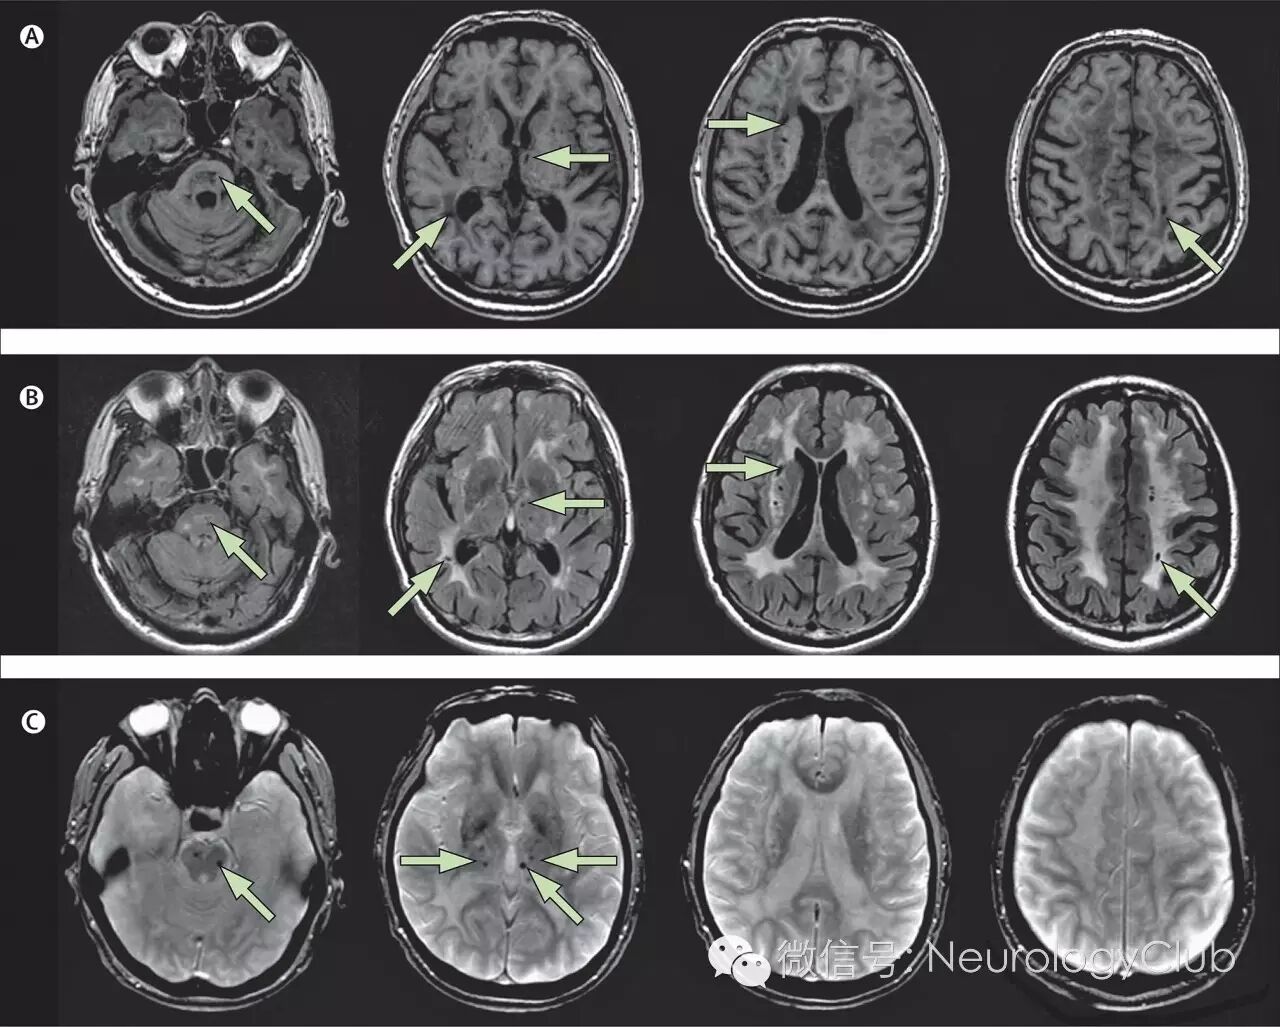

(图7:T1WI可见脑干,丘脑和豆状核等处多发腔隙性梗死;B:FLAIR上可见深部小梗死灶伴累及前颞叶和外囊的弥漫融合的白质高信号;C:T2*可见丘脑和脑干多发小的低信号病灶,为微出血)

(图9:A:颞极高信号病变;B:皮质下、外囊高信号病变;C-D:两例患者均有胼胝体受累[箭头])